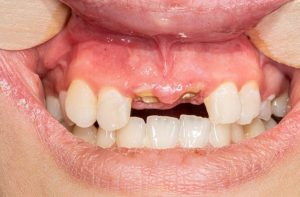

از جمله علائم پس زدن ایمپلنت های دندانی توسط بدن عبارتند از:

ایمپلنت دندانی “رد شده” یا “پس زده شده” به طور دقیق تر به عنوان یک ایمپلنت دندانی ناموفق توصیف می شود که یک عارضه نادر اما محتمل است و زمانی می تواند رخ دهد که سیستم ایمنی بدن نتواند ایمپلنت را بپذیرد. علائم می توانند کمی پس از جراحی یا سال ها بعد بروز پیدا کنند و معمولاً ناشی از عفونت، تراکم ناکافی استخوان یا بهبودی ضعیف هستند. علائم رد ایمپلنت ممکن است شامل موارد زیر باشند:

قطعاً روش درمانی ایمپلنت نیز در کنار مزایای متعدد خود، مانند دیگر روش های درمانی عوارضی احتمالی به همراه دارد. این عوارض پس از گذشت چند روز یا چند هفته در بدن فرد ظهور پیدا می کنند. علائم و نشانه های این عارضه در تمام افراد یکسان نمی باشند. مهم ترین عارضه ایمپلنت ایجاد درد در ناحیه فک و بین دندان ها می باشد. اگر شما قبل از انجام ایمپلنت یا همزمان با آن دندان خود را کشیده باشید احتمالا با دردهای شدیدتری روبه رو خواهید شد. خوب است بدانید این موضوع که کدام دندانتان را ایمپلنت می کنید نیز در بروز عارضه ها بسیار تأثیرگذار هستند. به عنوان مثال فردی که دندان های جلویی خود را ایمپلنت می کند قطعاً با مشکلات احتمالی بیشتری روبه رو خواهد شد.